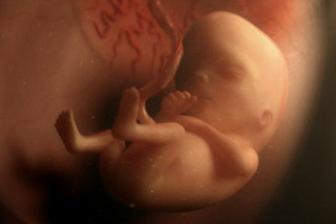

Jak asi víte, těhotenství je členěné na tři časové úseky, kterým říkáme trimestry – každý z nich trvá tři měsíce. Každý z trimestrů je zcela specifický, probíhají v něm určité charakteristické změny, podstupuje se vyšetření a nesou s sebou jiné pocity a obavy nastávající maminky.

Druhé tři měsíce těhotenství jsou pro spoustu žen nejkrásnějším a nejpříjemnějším obdobím za celou dobu těhotenství.

Lékaři počítají týdny těhotenství od prvního dne poslední menstruace před otěhotněním. V prvních dvou týdnech tehotenství tedy žena těhotná není, protože k oplodnění vajíčka dochází až zhruba 14 až 21 dní od začátku menstruace.